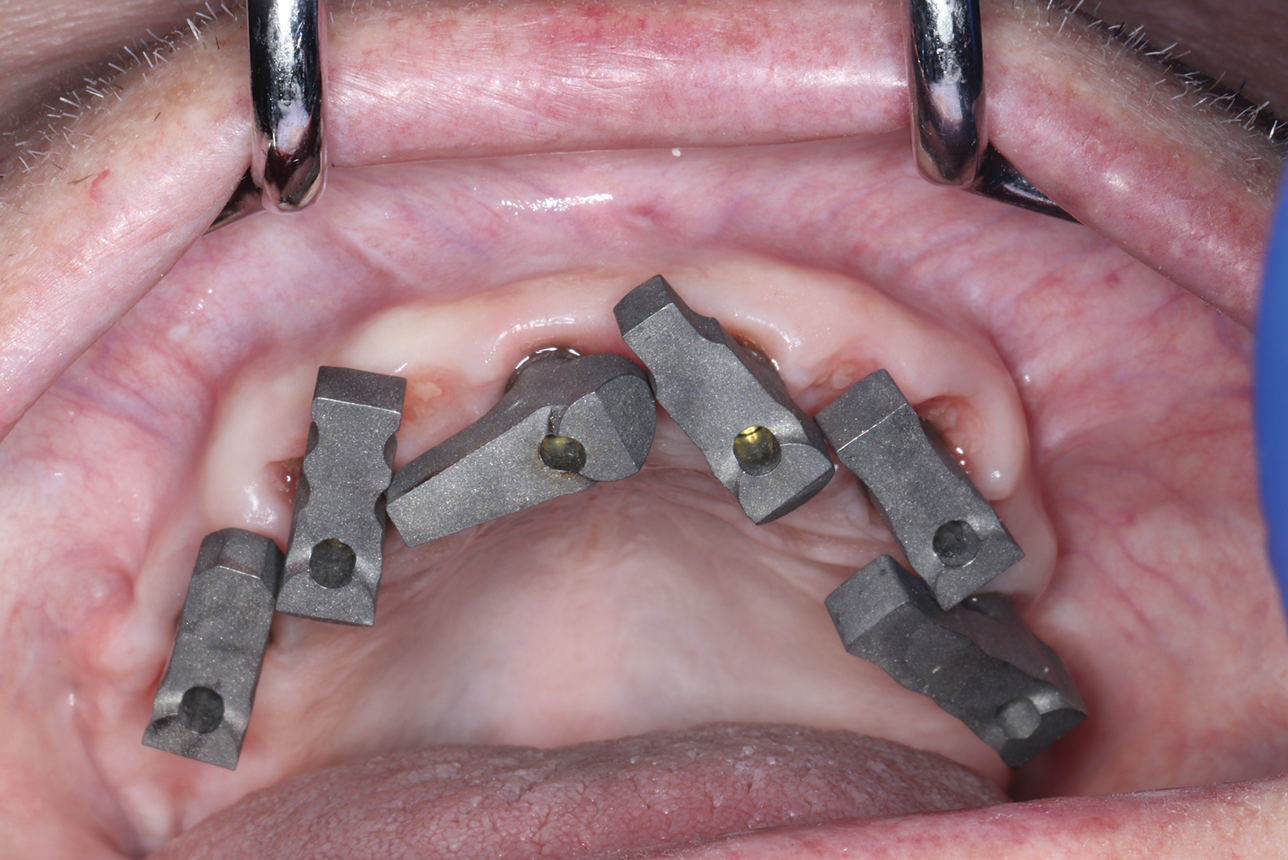

(10.) Scan bodies captured by photogrammetry that are ready for exportation to CAD software.

Figure 10

(11.) Sophisticated scan bodies with extensions that allow a mesh to be bonded for stability. The inset shows the structure rendered in CAD software.

Figure 11

Overcoming the obstacle of stitching together images with overlapping scan bodies and tissue has long impeded the accuracy of intraoral full-arch implant capture. However, a successful solution has been developed using dental photogrammetry systems (eg, iMetric iCam4D, Voxel Dental; PIC System, PIC Dental; MicronMapper, SIN 360). Photogrammetry involves attaching implant markers (ie, scan bodies, scan flags) to multi-unit abutments and then capturing multiple images from various angles using an extraoral optical scanner (Figure 8 through Figure 10).8 These images are then input into CAD software, matched to intraoral scans, and processed to create highly accurate virtual 3D models of arches and their surrounding structures. After inputting the data, technicians can seamlessly design tooth setups using a fully digital workflow.